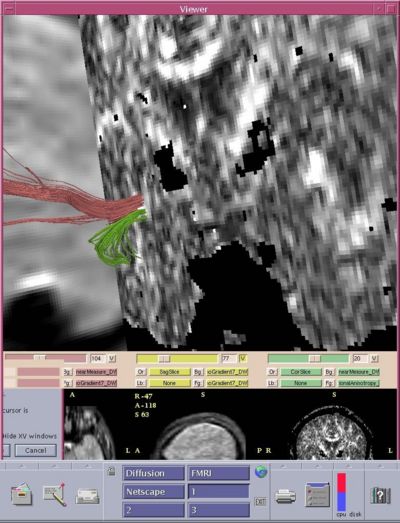

We followed up the ROI analysis of UF in chronic patients, in 27 chronic schizophrenics and 34 controls using a fiber-tracing method to estimate FA along the entire tract. We used two region-of-interest (ROI) extraction method, where we extracted fiber tracts traveling between two, manually drawn ROIs. First ROI was placed in the area previously investigated in our UF paper (Kubicki et al., 2002), second and third ROIs were placed within the temporal pole white matter, and posterior temporal white matter respectively. This resulted in two tracts, both traveling through the temporal stem, but separating their paths shortly after (Uncinate Fasciuclus (UF) and Inferior Occipito-Frontal Fasciuclus (IOFF)).